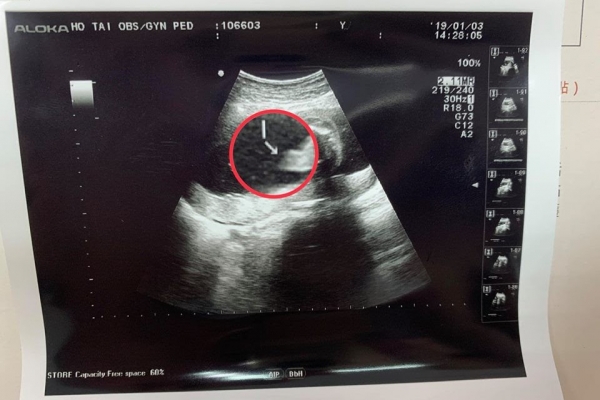

電話掛掉之後,媽媽實在是有夠尷尬,醫生還調侃:「剛剛那個是爸爸齁?」、「來啦!我照個鳥鳥特寫給他回去比對,看看他兒子的有沒有遺傳到他!」沒想到照片公開後,網友全都笑翻了!